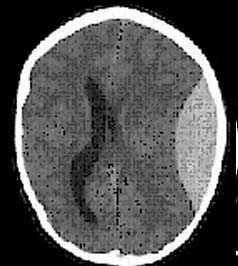

КТ-картина диффузного аксонального поражения мозга характеризуется увеличением объема мозга, в результате которого под сдавлением находятся боковые и III желудочки, субарахноидальные конвекситальные пространства, а также цистерны основания мозга. Нередко выявляют наличие мелкоочаговых геморрагий в белом веществе полушарий мозга, мозолистом теле, подкорковых и стволовых структурах.